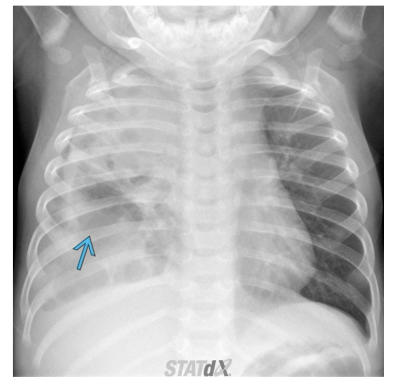

What CXR radiographic findings are typical for round pneumonia

• Spherically shaped consolidations in the posterior lower lobes, mostly seen in patients younger than 8

What are some usual causes for round pneumonia?

• Common agents are haemophilus influenzae, streptococcus, pneumococcus